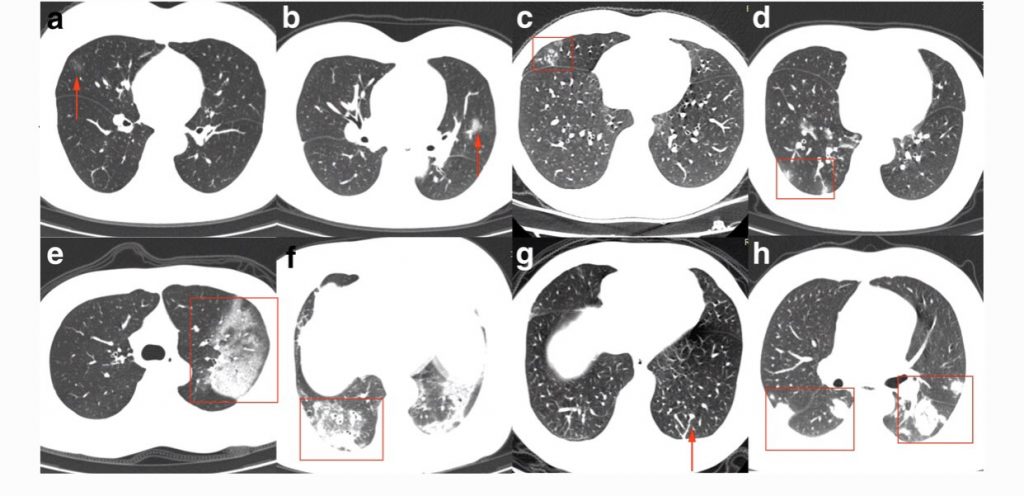

De beelden van de foto’s wisselen, maar in het algemeen ziet men in verschillende longgebieden ontsteking, zoals hier: pic.twitter.com/PeGH8caDbI

— Sander de Hosson (@shossontwits) March 1, 2020

De witte gebieden met pijltjes zijn de gebieden van de longontsteking, die op deze foto zwart horen te zijn. U ziet uiteraard ook de bronchieën en de bloedvaten.